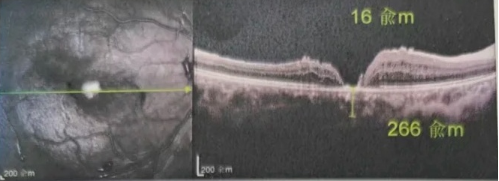

去年年底,年逾7旬的吳爺爺突然發(fā)現(xiàn)右眼看不清,且看東西變形,到當(dāng)?shù)蒯t(yī)院檢查后確診黃斑裂孔。此后他輾轉(zhuǎn)求醫(yī),經(jīng)歷了兩次玻切聯(lián)合內(nèi)界膜剝除術(shù),每次術(shù)后都嚴(yán)格“趴睡”一個月。然而結(jié)果令人失望:裂孔不但沒閉合,反而持續(xù)擴(kuò)大,甚至還并發(fā)高眼壓。

由于自身患有頸椎病,每次術(shù)后長期的趴睡都讓他痛苦不堪。為了尋求更好的治療,吳爺爺來到廈門大學(xué)附屬廈門眼科中心,找到了眼外傷及眼底病2科的李海波博士后。此時,吳爺爺右眼的黃斑裂孔已經(jīng)持續(xù)擴(kuò)大到780μm,演變?yōu)殡y治性的大裂孔。

最讓吳爺爺難以置信的是:術(shù)后只需保持平躺24小時!第二天復(fù)查時,眼底鏡及OCT檢查清晰顯示——那個折磨了他大半年的大裂孔,竟然閉合了!且吳爺爺?shù)挠已垡暳τ辛嗣黠@的改善,術(shù)后3天已經(jīng)可以看到 0.15。